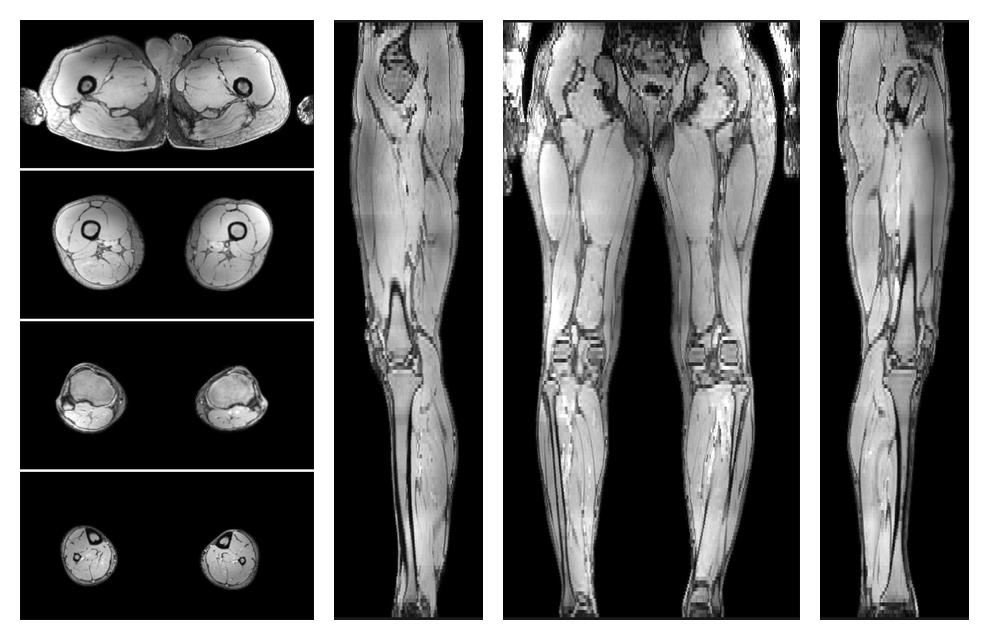

• Water only signal

The water part of the acquired multi-echo spin echo data.